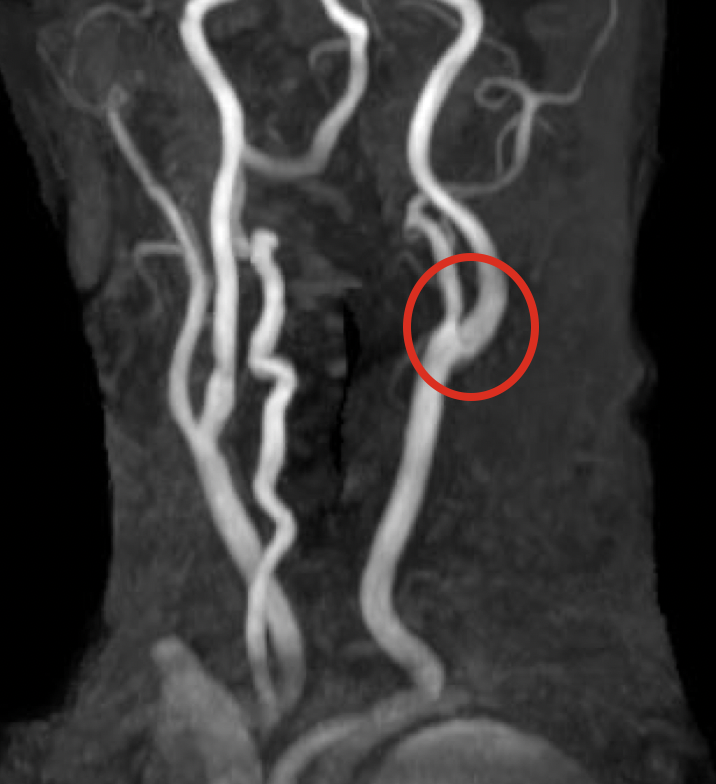

もやもや病の脳梗塞や出血リスク軽減のための血行再建術は、浅側頭動脈と中大脳動脈を直接つなぐ直接バイパス術を中心に、筋膜や筋肉を用いた間接バイパス術を組み合わせ、個々の患者に合わせた最適な術式が選択されます。これにより脳血流の改善と脳虚血や出血の予防を目指します。

バイパス術

術後MRA